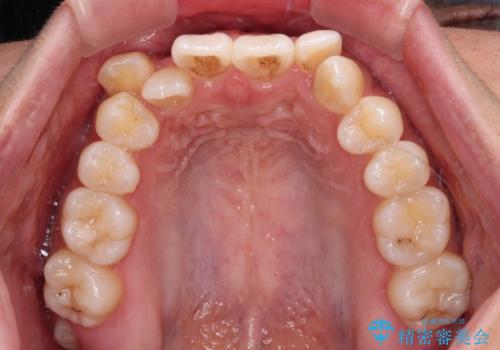

八重歯とオープンバイト 急速拡大装置を用いた矯正治療

- 前歯の開咬と、上顎前歯の八重歯やデコボコを気にして来院された患者様です。

上顎歯列が狭窄していたため、急速拡大装置により上顎骨を側方に拡大し、その後ワイヤー装置にて矯正治療を行うこととしました。